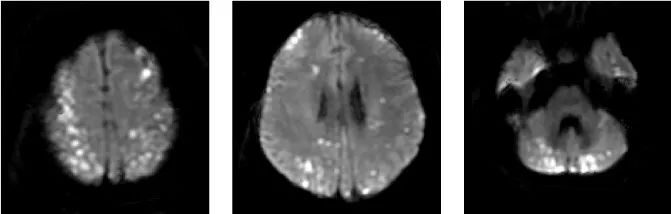

典型影像学表现:DWI 上病灶累及 3 个或 3 个以上血管分布区,常累及前后循环,双侧多见。排除其他明确的栓塞源或与这些病变相关的其他疾病。

2. 特发性嗜酸性粒细胞增多综合征(IHES):

导致多器官损害的白细胞增殖性疾病

排除感染、血液恶性肿瘤和血管炎后的排除诊断

IHES中的梗死是由于微血管闭塞而发生的,且多发于分水岭区。